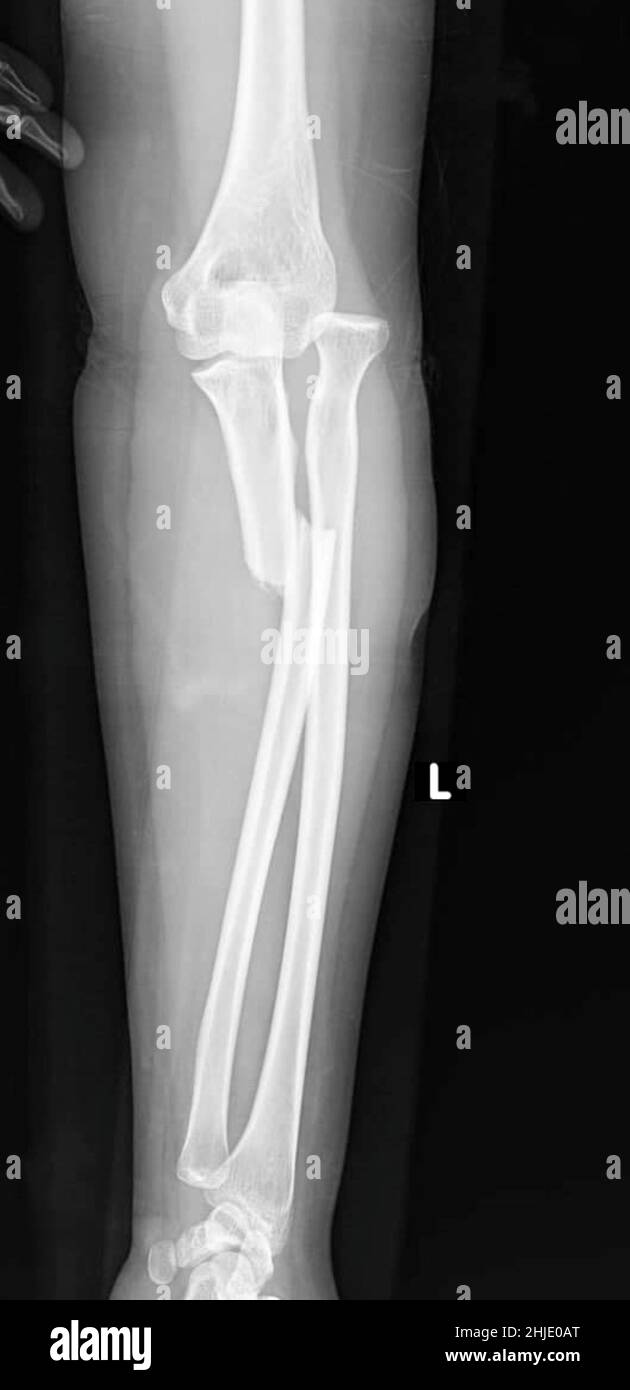

Monteggia Fracture X Ray . A monteggia fracture is defined as a proximal 1/3 ulna fracture with an associated radial head dislocation. The monteggia fracture is a fracture of the proximal ulna associated with dislocation of the radial head. Ap, lateral of elbow, forearm, wrist. Fractures involving coronoid, olecranon, and radial head. Diagnosis is made with forearm and elbow radiographs to check for. Monteggia involves fracture of the ulna with proximal radial dislocation. Proximal 1/3 ulna fracture + radial head dislocation (due to ulna. Galeazzi involves fracture of the radius with distal radioulnar. An examination starts with the visual inspection of the skin, soft tissue, visible bony deformity, skin lacerations, muscle contusion and.

[Figure, An xray of right forearm showing Monteggia fracture

[Figure, An xray of right forearm showing Monteggia fracture Monteggia Fracture X Ray A monteggia fracture is defined as a proximal 1/3 ulna fracture with an associated radial head dislocation. An examination starts with the visual inspection of the skin, soft tissue, visible bony deformity, skin lacerations, muscle contusion and. Fractures involving coronoid, olecranon, and radial head. Diagnosis is made with forearm and elbow radiographs to check for. The monteggia fracture is a. Monteggia Fracture X Ray.